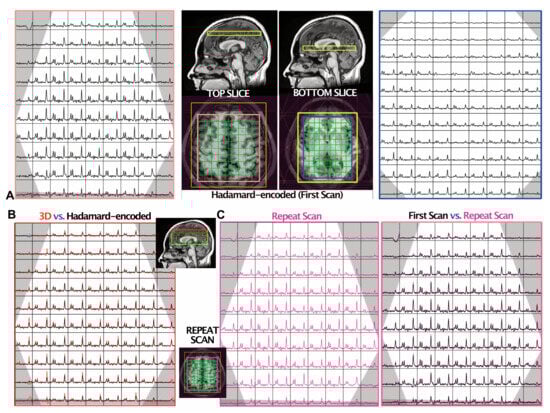

3.1. Dual-Slice Localization Using Hadamard Encoding

3.2. SNR and Reproducibility of Simultaneous Dual-Slice MRSI

3.3. GABA-Edited Dual-Slice MRSI